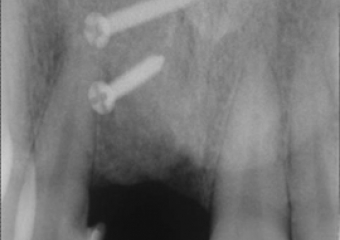

Raio X após o enxerto ósseo